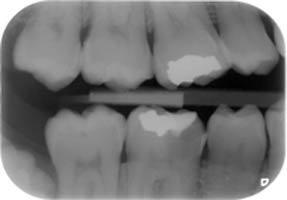

La endodòncia és la part de la odontologia que tracta la pulpa dental (o nervi de les dents). Aquesta pulpa està localitzada en un sistema de conductes radiculars que tenen les dents.

La majoria de vegades, les patologies que afecten la pulpa dental són produides per grans càries. Quan això succeeix, es produeix una inflamació o necrosis del teixit de la pulpa dental, i és necessària la extirpació d'aquesta. Això requereix un desbridament i conformació d'aquests conductes, i una obturació o segell dels mateixos amb materials biocompatibles. Això és el que es coneix com una endodòncia, o vulgarment dit, "matar el nervi".

Aquest tractaments és complexe. Normalment, es pot realitzar en una visita, tot i que de vegades es necessitin més segons la complexitat del cas (nombre d'arrels del queixal, corvatura i longitut, de les mateixes, calcificacions de la pulpa, etc.)